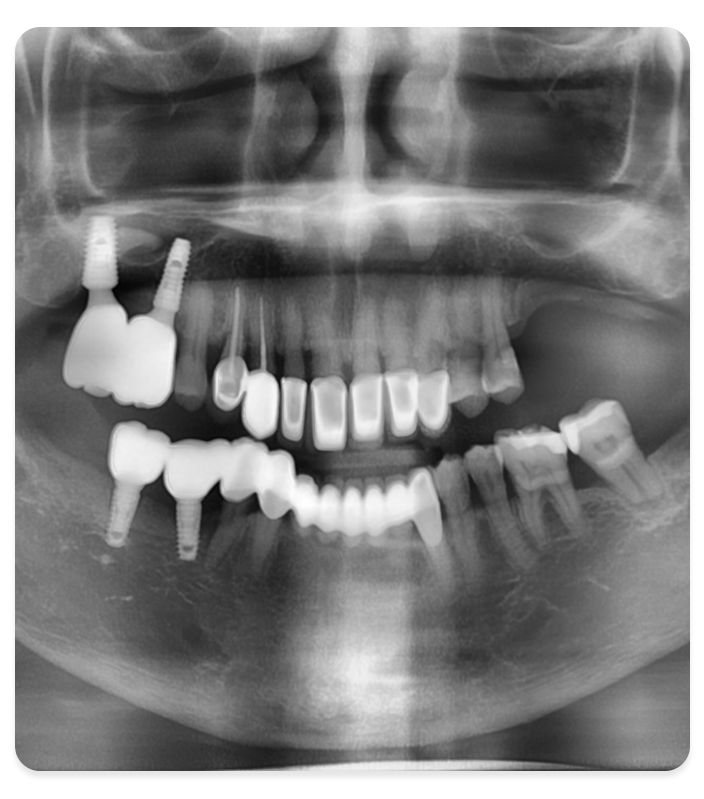

3D 진단·치주 평가

CBCT 촬영 및 잇몸 상태 정밀 검사

02

수술 계획·가이드 제작

디지털 플래닝 및 서지컬 가이드 제작